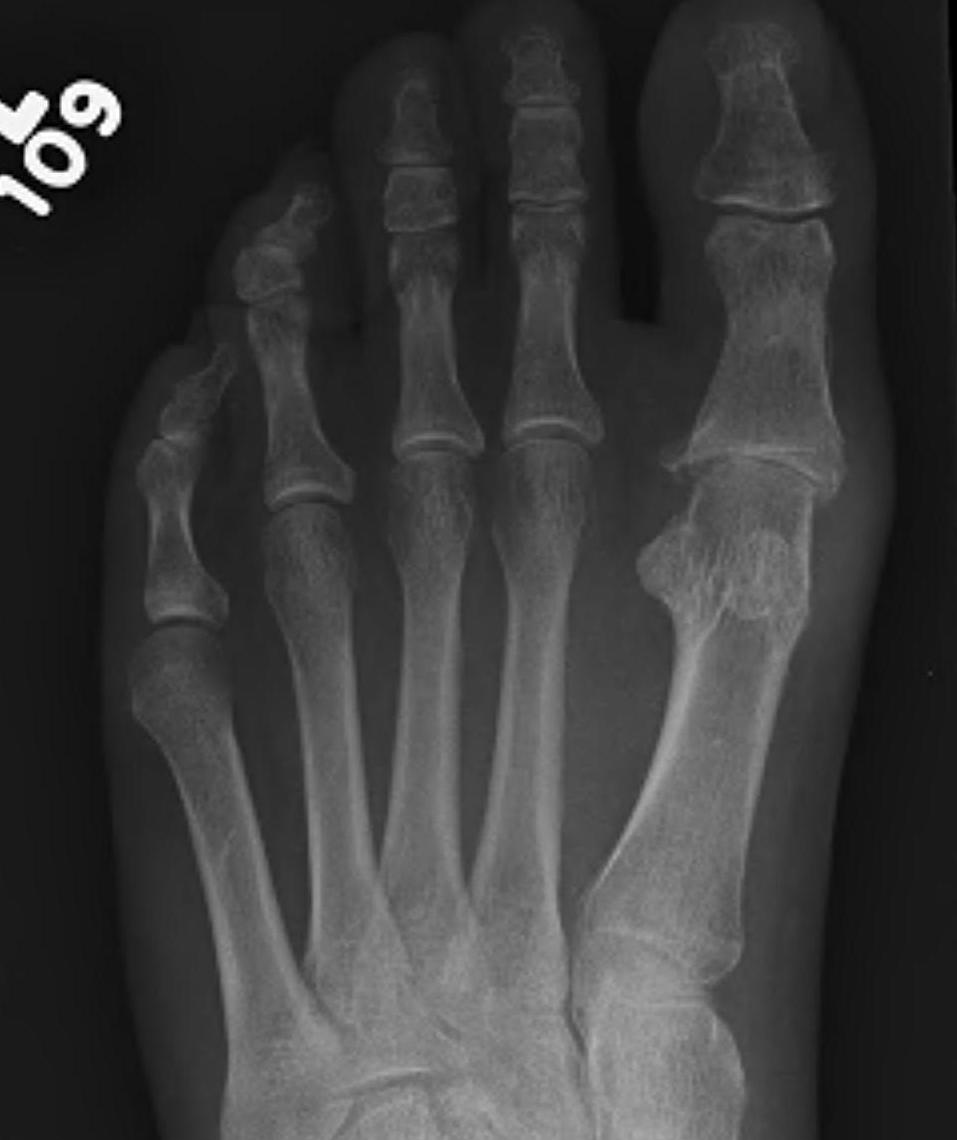

X-ray

Osteoarthritis

- joint space narrowing

- dorsomedial osteophyte

Severe OA